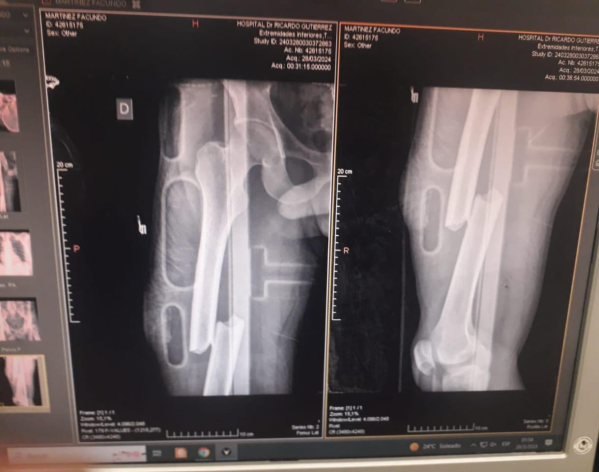

“Tuvo un accidente en 12 y 58 mientras repartía. Se le cruzó en un auto y se fracturó en dos partes el fémur. La prótesis que necesita sale 800 mil pesos”, contó Rocío.

“Él ahora está postrado. El doctor dice que la operación se tiene que hacer dentro de los 21 días. Por eso es que pedimos la plata. Hay gente en el hospital esperando hace dos meses y no queremos correr el riesgo de que le quede mal la pierna”, señaló Rocío.